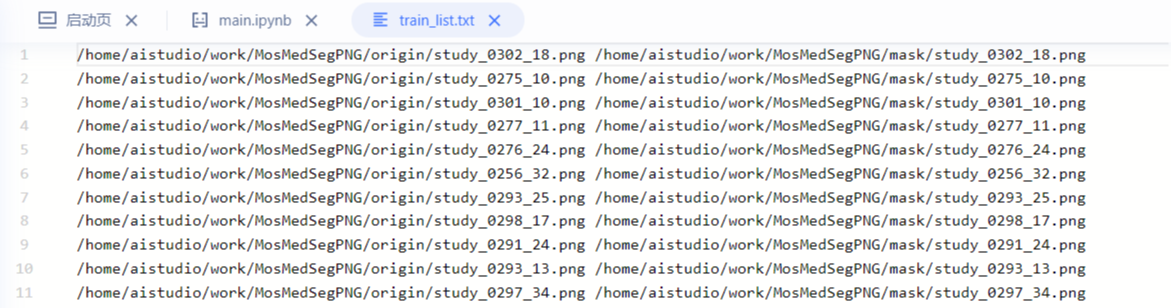

划分数据,生成txt文档

每一行由两个文件路径+空格组成。第一个路径是原始图片的路径,第二路径是mask路径。这里的路径采用绝对路径,这样做会避免在搭建Dataset时填写参数"dataset_root" 与"train_path"的搭配问题。例如采用绝对路径后,就不用关心"dataset_root"的设置。

### 划分数据集

random.seed(1000)

path_origin = '/home/aistudio/work/MosMedSegPNG/origin'

files = list(filter(lambda x: x.endswith('.png'), os.listdir(path_origin)))

random.shuffle(files)

rate = int(len(files) * 0.8)#训练集和测试集8:2

train_txt = open('/home/aistudio/work/MosMedSegPNG/train_list.txt','w')

val_txt = open('/home/aistudio/work/MosMedSegPNG/val_list.txt','w')

for i,f in enumerate(files):

image_path = os.path.join(path_origin, f)

label_path = image_path.replace("origin", "mask")

if i < rate:

train_txt.write(image_path + ' ' + label_path+ '\n')

else:

val_txt.write(image_path + ' ' + label_path+ '\n')

train_txt.close()

val_txt.close()

print('完成')

完成